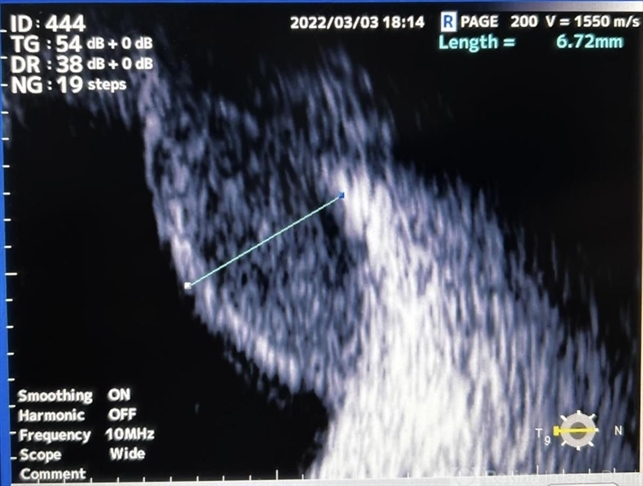

- Choroidal melanoma

- B-mode